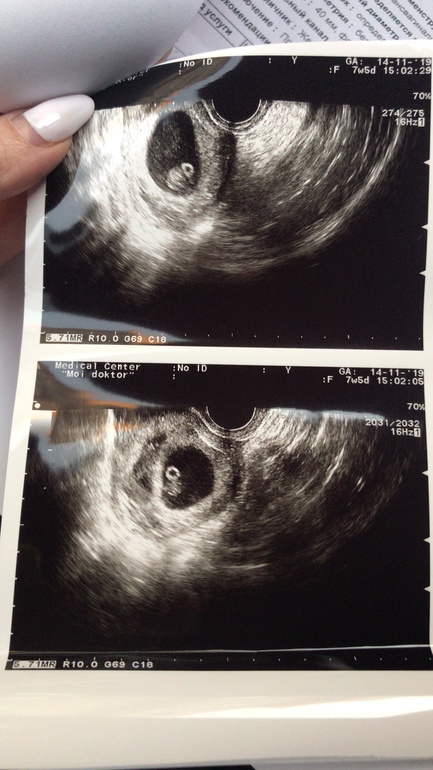

Сходила сегодня на повторное УЗИ. Сказать что я в шоке, это ничего не сказать.....у меня ДВОЙНЯ!!!!!!! 👬

Две недели назад было одно плодное яйцо. Я просто в шоке откуда второй эмбрион🙈